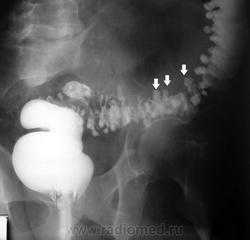

Классическим показанием к рентгенологическому исследованию желудка является диагностика язв желудка и 12-перстной кишки. Язвы желудка чаще всего локализуются на малой кривизне, а 12-перстной кишки - в области ее луковицы. Однако возможна любая локализация язв. Наиболее надежными рентгенологическими симптомами язв являются симптомы «ниши» и «кратера», локальные изменения рисунка слизистой, отек и ригидность стенки в месте локализации язвы

Рентгенография хорошо выявляет последствия язвенной болезни - участки рубцовой деформации желудка и 12-перстной кишки. Иногда язвы могут осложняться пенетрацией в окружающие органы (поджелудочную железу, печеночно-дуоденальную связку, сальник, печень и желчные пути), а также в брюшную полость. В этом случае при обзорной рентгенографии или при выполнении снимка на правом боку (латерография) выявляется свободный воздух в брюшной полости, указывающий на перфорацию полого органа. Следует заметить, что при подозрении на перфорацию одного из органов пищеварительного канала противопоказан прием бария. Для контрастирования органов пищеварительного канала в этом случае используют водорастворимые йодсодержащие контрастные вещества. Диагностика перфораций и сопутствующих им осложнений возможна также с помощью УЗИ и КТ.

Рентгенография и рентгеноскопия остаются важными методами диагностики доброкачественных и злокачественных опухолей желудка. Их дифференциальная диагностика основывается на анализе контуров опухоли, характера изменений складок желудка и локальной ригидности его стенок